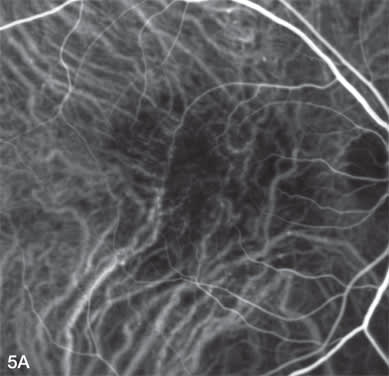

Standard fluence verteporfin photodynamic therapy (PDT) causes choroidal hypoperfusion, which is easily documented by ICGA. This can be helpful to titrate fluence of repeat PDT when used in combination therapy with an anti-VEGF therapy. While mild choroidal hypoperfusion may not be harmful to ultimate VA, those patients with profound VA loss typically have profound choroidal ischemia. Figures 5A-5C demonstrate an early, mid, and late phase ICG 1 week after 40% fluence verteporfin PDT treatment in combination with intravitreal ranibizumab. This particular patient had persistent choroidal hypoperfusion up to 6 months following PDT treatment but maintained 20/25 VA.

Figure 5A, B, and C. Early, mid, and late-phase ICG demonstrate marked choroidal hypoperfusion one week after reduced fluence verteporfin photodynamic therapy.